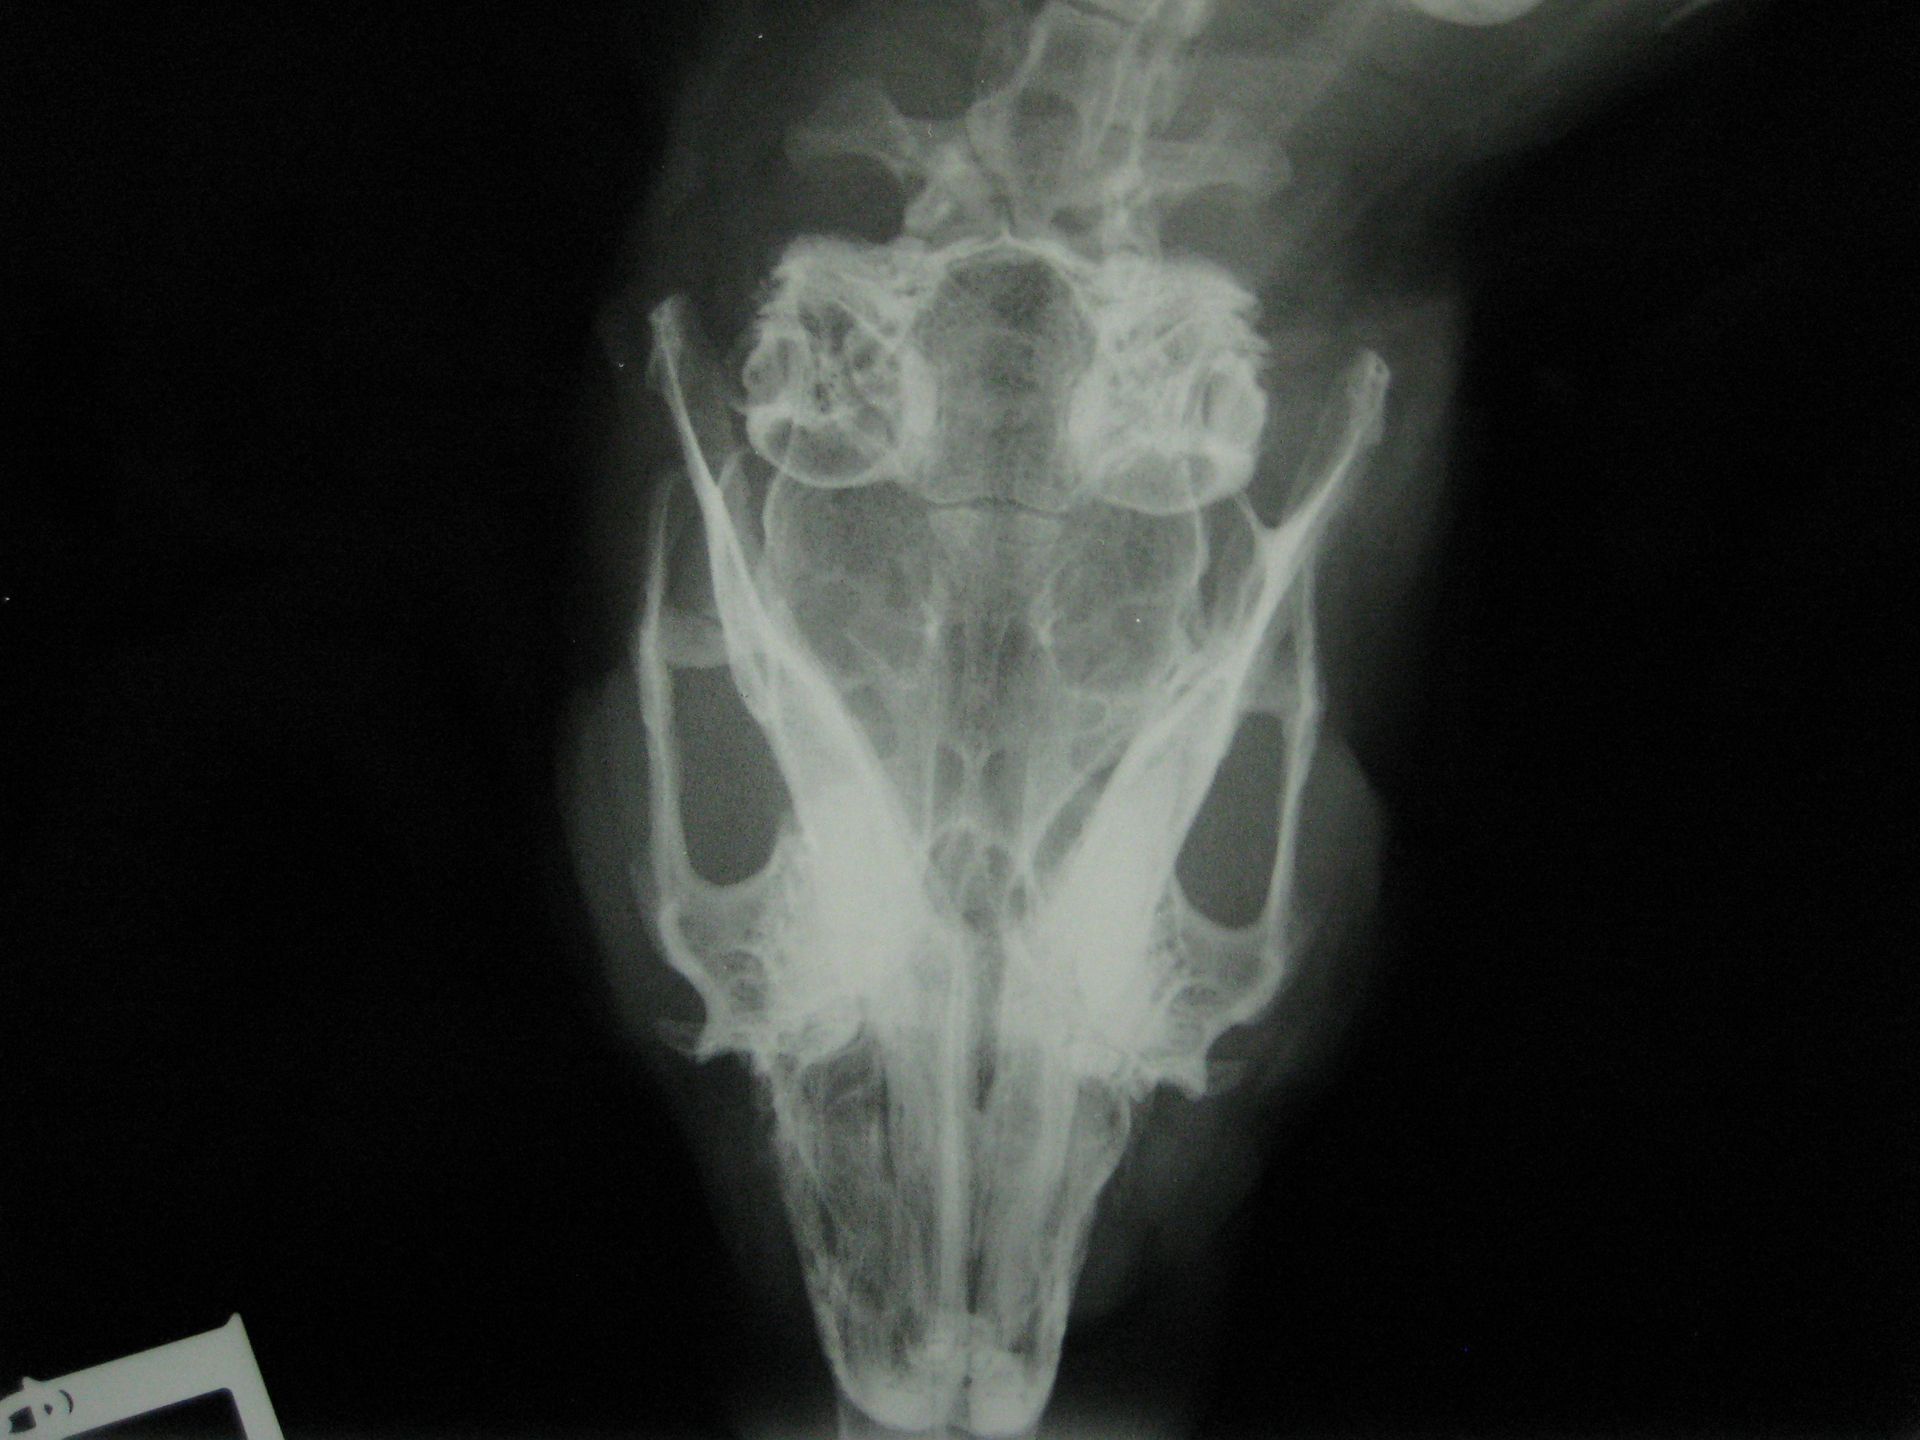

Pour déterminer l'origine et les caractéristiques de l'abcès, l'idéal est de réaliser un examen d'imagerie précis comme le scanner. Le scanner correspond à un examen radiographique en trois dimensions. Le traitement de choix est typiquement chirurgical et médical. Certaines de ces chirurgies peuvent être particulièrement complexes et nécessiter l'utilisation d'un endoscope.

Le diagnostic est relativement aisé par radiographie. Cependant, toutes les sabloses ne sont pas nécessairement pathologiques. Un bilan complet associant prise de sang et échographie est recommandé. Le traitement passe par une amélioration de l'hydratation et des rectifications alimentaires. Cette sablose peut prédisposer aux calculs vésicaux, urétéraux ou rénaux.

Le diagnostic se fait par radiographie mais une échographie et une prise de sang sont recommandés pour exclure la présence d'autres calculs au niveau des uretères et des reins et aussi pour vérifier l'absence d'insuffisance rénale. Le traitement est quasiment toujours chirurgical, certains cas particulier peuvent être traité par endoscopie ou par traitement médical.

Une infection par E.cuniculi peut éventuellement prédisposer à la formation de calculs. Les calculs rénaux se voient généralement à la radiographie mais certains calculs ne peuvent être visualisés que par échographie.